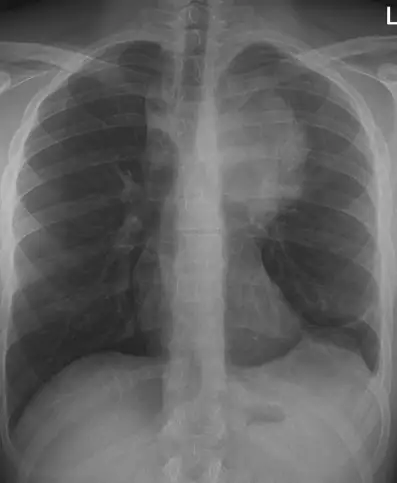

On examination, vital signs are within normal limits. The patient appears well and not in acute distress. Lung auscultation was clear bilaterally, and the remainder of the initial physical exam is unremarkable. A chest radiograph (anteroposterior and lateral views) is obtained.

Review the anteroposterior chest x-ray image and consider what your diagnosis and next steps would be. Resolution of the case is described on the following page.